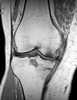

Osteonecrosis of the medial tibial condyle

Spontaneous osteonecrosis of the Knee, is the result of vascular arterial insufficiency to the medial femoral condyle of the knee resulting in necrosis and destruction of bone. It is often unilateral and can be associated with a meniscal tear. [Source: Wikipedia ]